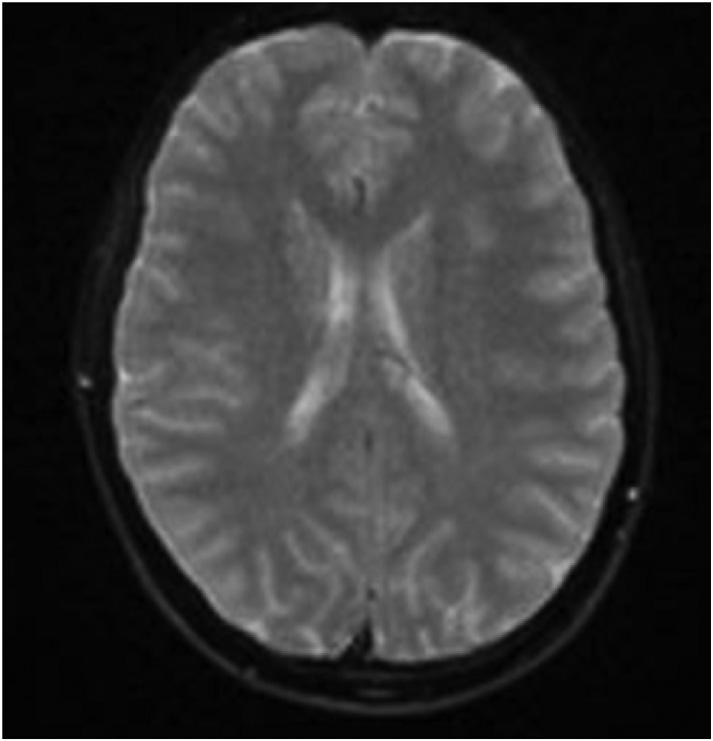

mayindicategasemboluswithpossibleevolvinginfarctionin therightparietalregion.Nohemorrhageorshift.Further evaluationwithmagneticresonanceimaging[MRI]maybe useful.Largegoiter.” Immediatelytheteamassessedthe patient’scentralvenouscatheterandfoundanuncappedline. Aftertheairwaswithdrawnfromtheline,thelinewas capped.Thepatientwastransferredtotheintensivecareunit atourhospitalforfurthermanagementandahyperbaric medicineconsultation.Heunderwentahyperbaricoxygen therapytreatmentwithresolutionofthegasontherepeatCT head.Afollow-upMRIrevealedmultifocalinfarctsin multiplevascularterritories.